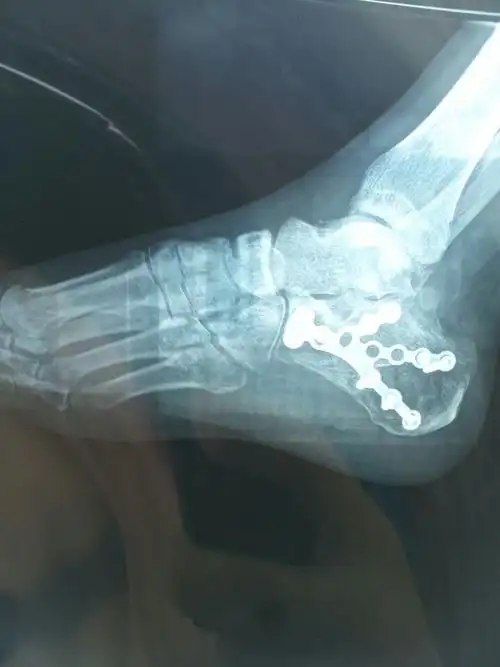

"香港新一代玉女"卫诗雅滑雪时发生意外:脚骨裂了五分之四!